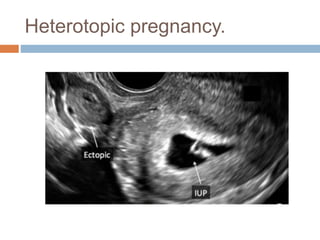

Heterotopic pregnancy.